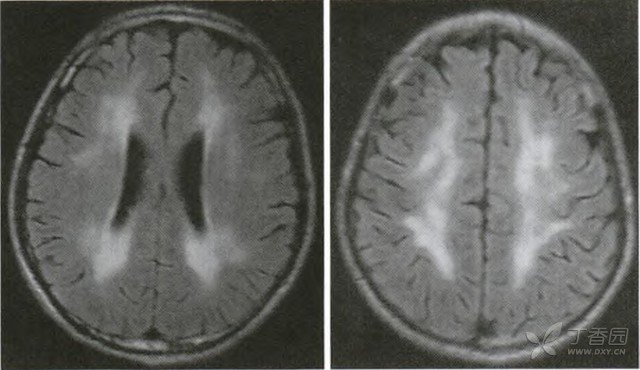

即线粒体脑肌病伴乳酸血症和卒中样发作等一组临床症状,多为母系遗传。10岁前发育正常。10~40岁发病,首发症状为运动不耐受、卒中样发作、偏轻瘫、失语、皮层盲或聋。并有肢体无力、抽搐或阵发性头痛、智能低下、痴呆及乳酸血症,肌活检见RRF、异常线粒体和晶格样包涵体。CT可见30%~70%苍白球钙化,MRI皮层有层状异常信号的特征所见。基因检测可见3243或3271核苷酸点突变。MELAS患者卒中样发作急性期主要累及颞顶或颞枕叶,病灶可累及皮质和深部的白质。与缺血性脑梗死不同,MELAS梗死灶与脑动脉灌注供血区分布不一致,主要集中在代谢旺盛的微血管区域,周围水肿不明显,伴有星型胶质细胞增生。MELAS患者累及神经系统的其他常见症状包括神经性耳聋、偏头痛、认知功能受损、周围神经病、抑郁及一些精神症状等。隐性起病的神经性耳聋常是MELAS的早期表现,常有家系遗传,在未发病的患者亲属中也可发生。随访研究发现超过半数的MELAS患者有不同程度的听力下降和母系遗传的糖尿病和/或耳聋(MIDD)。其次,发病前出现不规则的偏头痛也是MELAS患者早期的常见症状,头痛常发生在疾病的间歇期,推测可能是线粒体能量代谢受损,一方面增加了神经元的兴奋性,另一方面降低了诱发头痛的阈值所致。再次,MELAS患者发病时可有不同程度的认知障碍,包括语言、记忆、定向力障碍等。最常见是前额叶的执行功能受损,MRI上表现为脑干后部、扣带回的缺血样改变,可能与脑皮质神经元变性有关。另外,少部分患者可出现周围神经病,表现轻微感觉异常、袜套样麻木感等,以隐匿性、渐进性起病为主,常累及远端肢体。

即肌阵挛癫痫发作、小脑共济失调、乳酸血症和RRF,少数有智能低下、痴呆,亦有神经聋、矮小、弓形足等畸形。脑电图显示为棘慢波综合,肌活检见RRF、异常线粒体和包涵体。CT和MRI可见小脑萎缩和大脑白质病变。基因检测可见8344或8356核苷酸点突变。